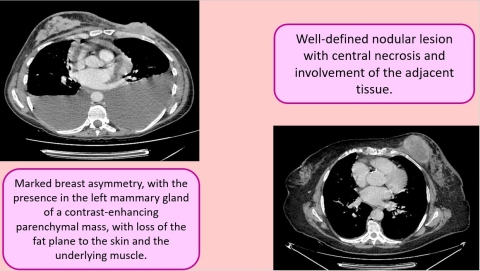

Invasive Breast Carcinomas: 3 interesting cases

Histopathological analysis ultimately revealed two cases of invasive ductal carcinoma (IDC) and one case of invasive lobular carcinoma (ILC), representing the most common and second most common subtypes of invasive breast malignancy, respectively.

The second IDC case involved a unilateral enhancing breast mass with associated ipsilateral axillary lymphadenopathy, without evidence of distant metastatic disease. The radiologic appearance was consistent with invasive ductal carcinoma, and histopathology confirmed the diagnosis following directed biopsy.

Fig 3.jpg

CT and Histology Highlights:

• Unilateral IDC: enhancing mass with ipsilateral lymphadenopathy, no distant metastases

• Biopsy confirmed all three invasive breast malignancies

• CT demonstrated capability to detect both primary tumors and advanced metastatic disease